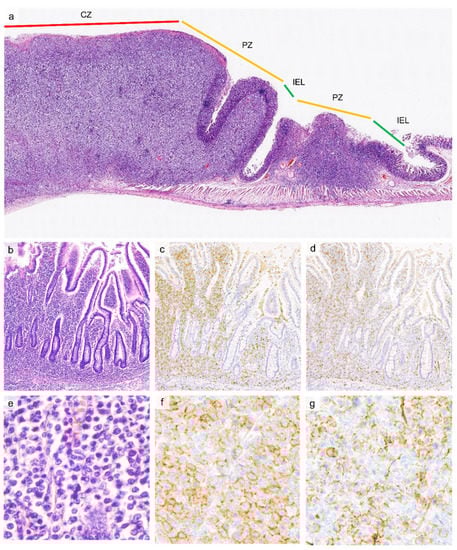

3.2. Histopathology

5.2. Histopathology